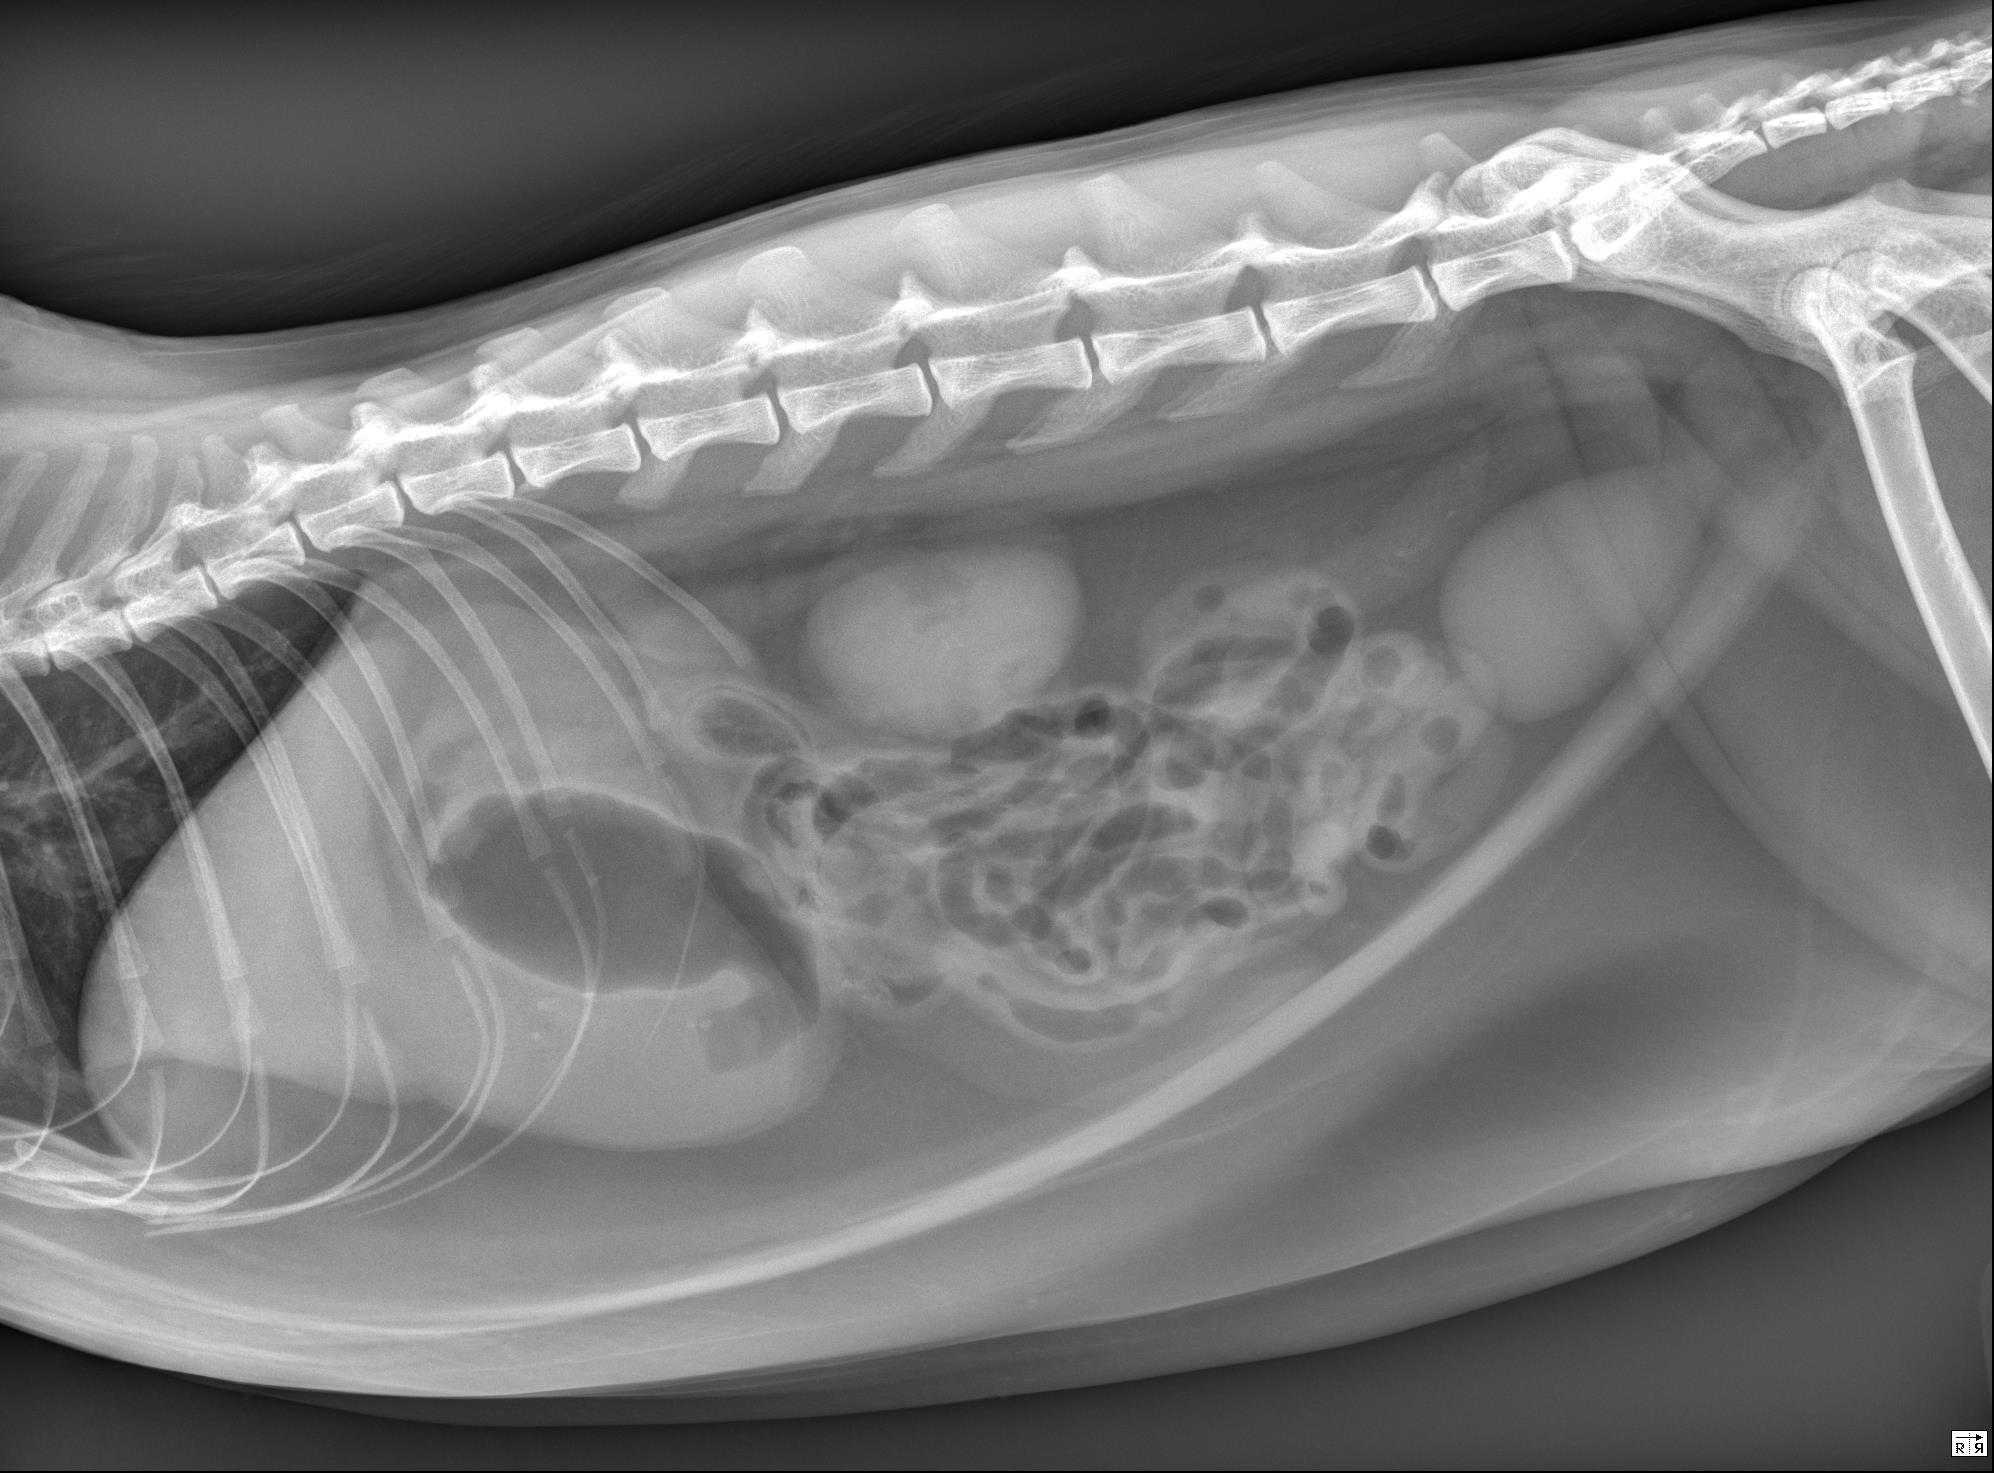

Study: Left lateral, right lateral, and ventrodorsal abdominal radiographs are available for review.

Findings: The stomach is distended with a large volume of fluid, a smaller volume of gas, and a small number of pinpoint, mineral opaque foci. In the orad duodenum, seen ventral to the last pair of ribs in the lateral views and to the right of L2 in the ventrodorsal view, there is an ovoid structure in the duodenal lumen. The structure is gas-filled with a soft tissue opaque border surrounded by a thin rim of gas. It measures approximately 2 cm in length and 1 cm in diameter. The duodenum orad to this structure is mildly distended while the duodenum aborad to this structure appears empty/small in diameter. The remainder of the small intestinal tract is mildly, uniformly distended with fluid and gas in a string of pearls pattern, consistent with peristalsis. The colon contains a small volume of nonformed stool. The serosal detail, liver, spleen, kidneys, retroperitoneal space, and urinary bladder are normal. The imaged skeletal structures and caudal thorax are unremarkable.

Conclusions: Ovoid structure (suspected gas-filled foreign body) in the orad duodenum causing intestinal obstruction. Surgical intervention is warranted.